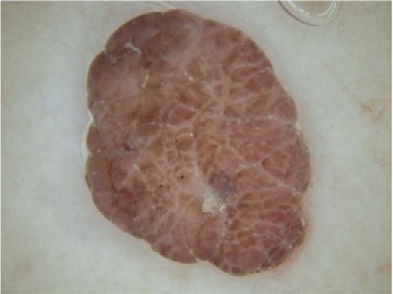

图1

使用大小为 7×7的非锐化滤波器的所提方法步骤:(A) 原始ISIC_0010447皮肤镜图像,(B) 去毛预处理后的图像,(C) 预处理图像的灰度版本,(D) 第一次迭代后的首个中性版本,(E)–(H) 最后一次迭代后的中性映射算子,分别为 (E) 最终真值图像T;(F) 最终不确定图像I;(G) 最终假值图像F;(H) 最终中性版本,(I) 输出的中性图像,(J) K均值聚类图像(无监督分割图像)。

图1展示了使用大小为 7×7的非锐化掩模滤波器进行中性映射时各阶段的相应图像。图1D显示了首先生成三个子集T, F,和I的皮肤镜中性图像,在第一次迭代后所示,其中在下一次迭代之前计算了熵值。随后,创建了这三个子集,并计算其熵值,与先前获得的熵值进行比较。此过程反复执行,直到最近一次迭代的熵值与其先前熵值之间的差异除以前一个熵值小于 α optimal¼ 0.0014,即

满足条件,则终止迭代过程,并得到NS图像的最终T、F和I算子,如图1E–H所示。T, F, 和 I算子的中性集图像结果如图1E–H所示。